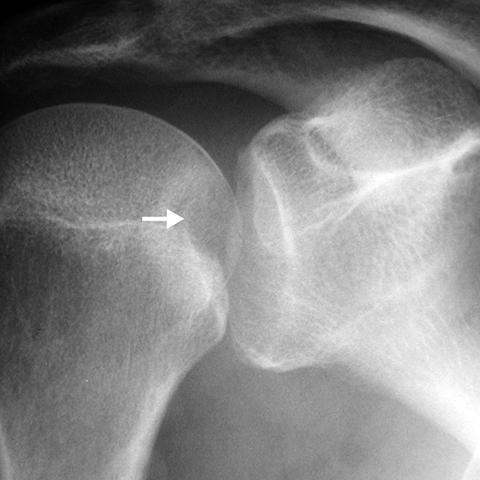

Reverse Hill-Sachs fracture